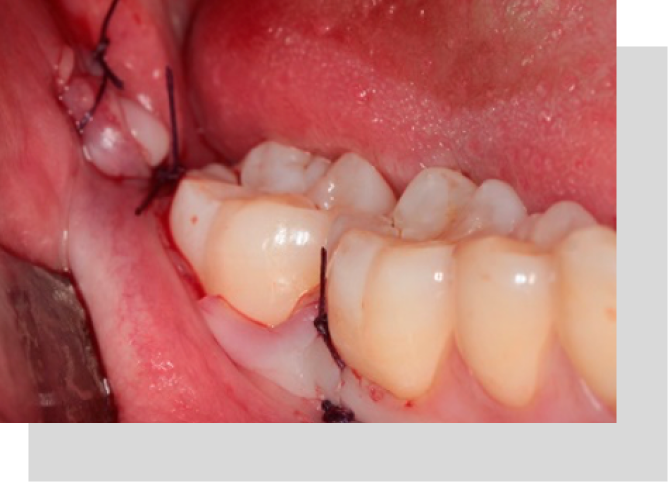

Biopsias

Se realizan biopsias ante lesiones orales sospechosas que duren mas de 15 días, o que tengan algún aspecto anormal, procedimiento en donde se toma una pequeña muestra para estudio de las lesiones.

Frenectomías

Es la cirugía de los frenillos de la cavidad bucal, puede ser en los labios, lengua o encía lateral. Debe ser realizada por un cirujano en un pabellón de cirugía menor.